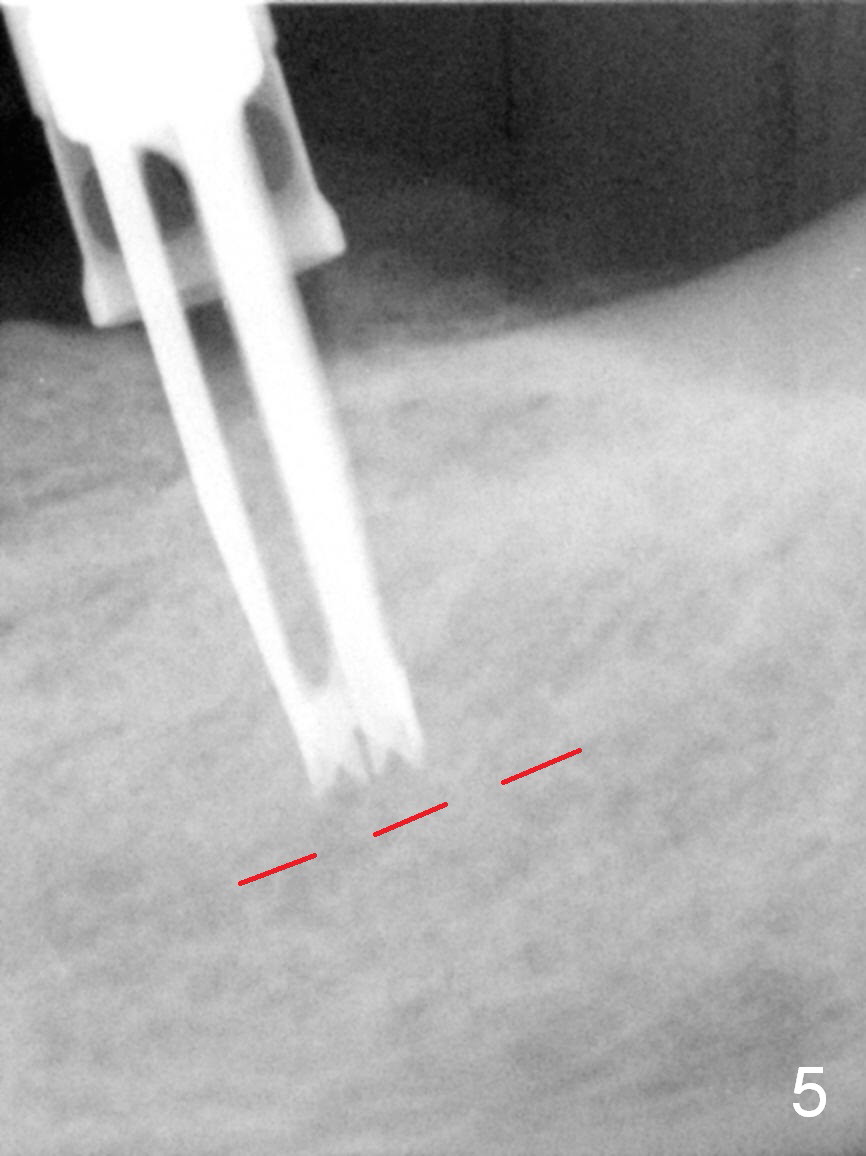

Except the tooth #30, the patient is completely edentulous (Fig.1,2). His chief complaint is "food gets into the missing tooth area". Due to short guide pin (Fig.3) and parallel pin (Fig.4), it is difficult to calculate precisely at the site of #19 the distance to the superior border of the Inferior Alveolar Canal (Fig.4 red dashed line). The clearance appears to be limited when a 4.3 mm drill is in place with 11 mm depth (Fig.5). Therefore an implant shorter than the last drill is placed (5x9 mm, Fig.6). Insertion torque is >50 Ncm. A 5x4(2) mm pair abutment is inserted temporarily to check occlusion with the opposing dentition (A). Finally a 5x2 mm healing abutment is placed with harvested autogenous bone placed between the implant and abutment (Fig.7). Before discharging the patient, the lower RPD is in place to check the position of the implant/abutment (Fig.8).